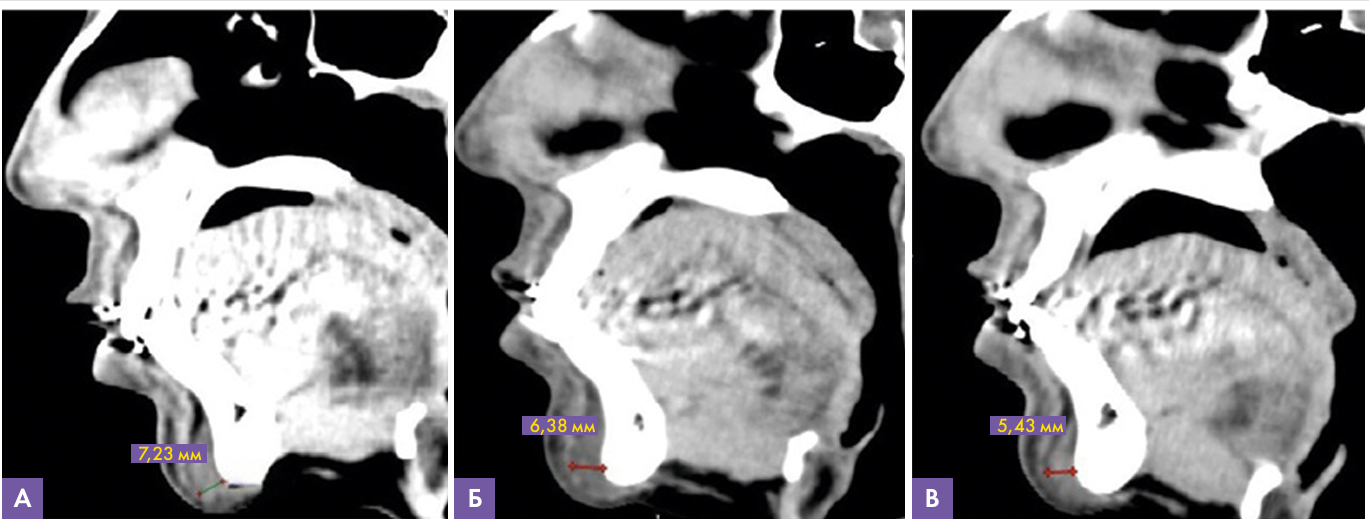

Данные МСКТ: на сагиттальных срезах подбородочной области (рис. 9) определяется имплантат, интимно прилежащий к подбородочному отделу нижней челюсти сзади и к подбородочной мышце спереди, в виде включений плотностью аналогичной плотности мышечной ткани. Толщина слоя жирового тела подбородка от костной структуры до подбородочной мышцы изначально составляла 4,8 мм, через 3 недели после инъецирования имплантата на основе гиалуроновой кислоты – 7,4 мм. При динамическом исследовании через 12 месяцев коррекции толщина вышеописанного слоя составляет 5,43 мм. Данных за наличие инфильтративных изменений, признаков миграции и инкапсулирования препарата не выявлено.

Рисунок 9. МСКТ сканы подбородочной области, сагиттальная проекция

А – через 5 месяцев, толщина имплантата 7,23 мм

В – через 9месяцев, толщина имплантата 6,38 мм

С – через 12 месяцев, толщина имплантата 5,43 мм